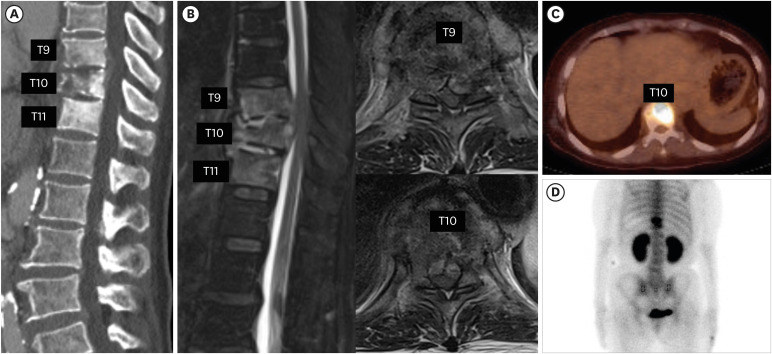

结核性脊柱炎,又称波特病,于1779年由珀西瓦尔·波特首次描述。由于感染的非特异性,结核性脊柱炎的诊断常常被推迟,这可能导致严重的后果。鉴别诊断对化疗后出现淋巴结或骨转移的癌症患者尤为重要。我们提出的情况下,76岁的女性胃癌晚期,谁最初怀疑有转移性脊柱肿瘤和细菌性脊柱炎。患者表现为下肢瘫痪,并被诊断为转移性癌症,导致失去康复的希望。然而,在随后的结核性脊柱炎诊断和多次手术干预后,患者完全缓解并显著改善,最终恢复了独立行走的能力。这个病例强调了准确诊断和及时干预的重要性,在病例的最初表现可能模仿转移性疾病。

Tuberculous (TB) spondylitis, also known as Pott's disease, was first described by Percivall Pott in 1779. The diagnosis of TB spondylitis is often delayed because of the non-specific nature of the infection, which can lead to severe consequences. Differential diagnosis is especially critical in cancer patients undergoing chemotherapy who present with lymph node or bone metastasis. We present the case of a 76-year-old female with advanced gastric cancer, who was initially suspected of having a metastatic spinal tumor and bacterial spondylitis. The patient presented with lower limb paralysis and was diagnosed with metastatic cancer, resulting in a loss of hope for recovery. However, following the subsequent diagnosis of TB spondylitis and multiple surgical interventions, the patient achieved complete remission and significant improvement, ultimately regaining the ability to walk independently. This case highlights the importance of accurate diagnosis and timely intervention in cases where the initial presentations may mimic metastatic disease.